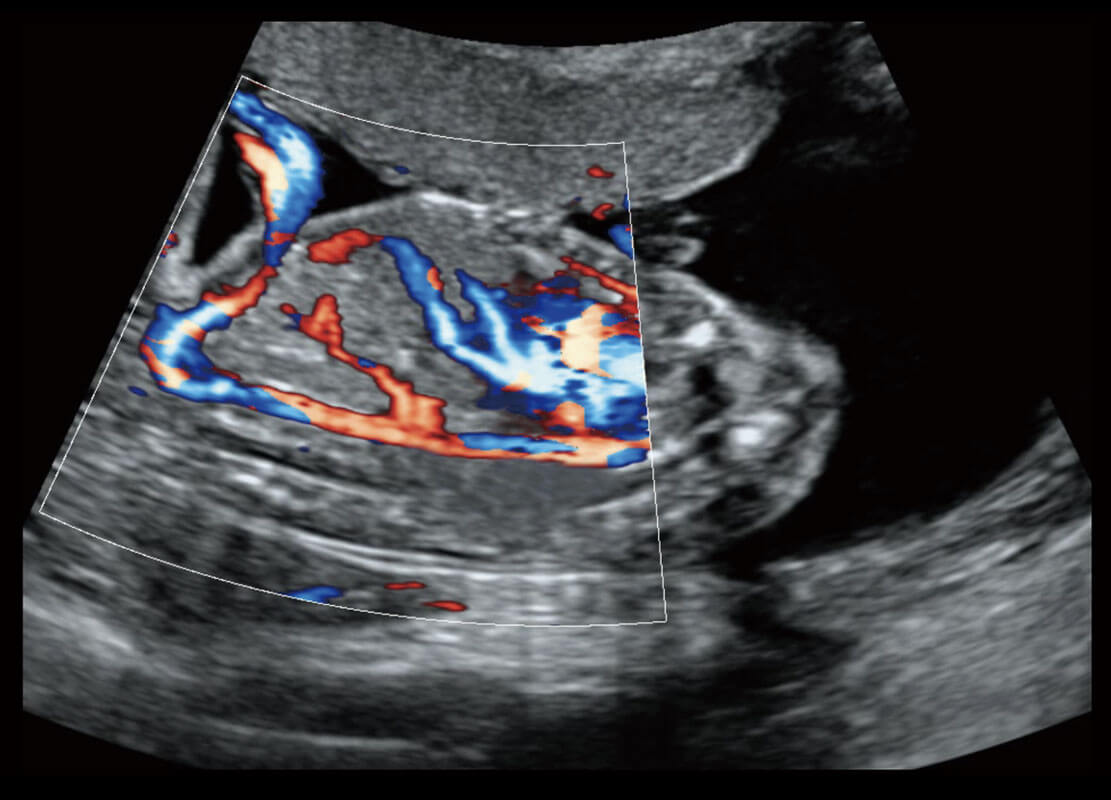

P60在胎儿早孕期超声筛查中为您带来优异的图像质量。

早孕-胎心

高分辨率容积成像-早孕胎儿

胎儿体循环

光影成像-孕囊